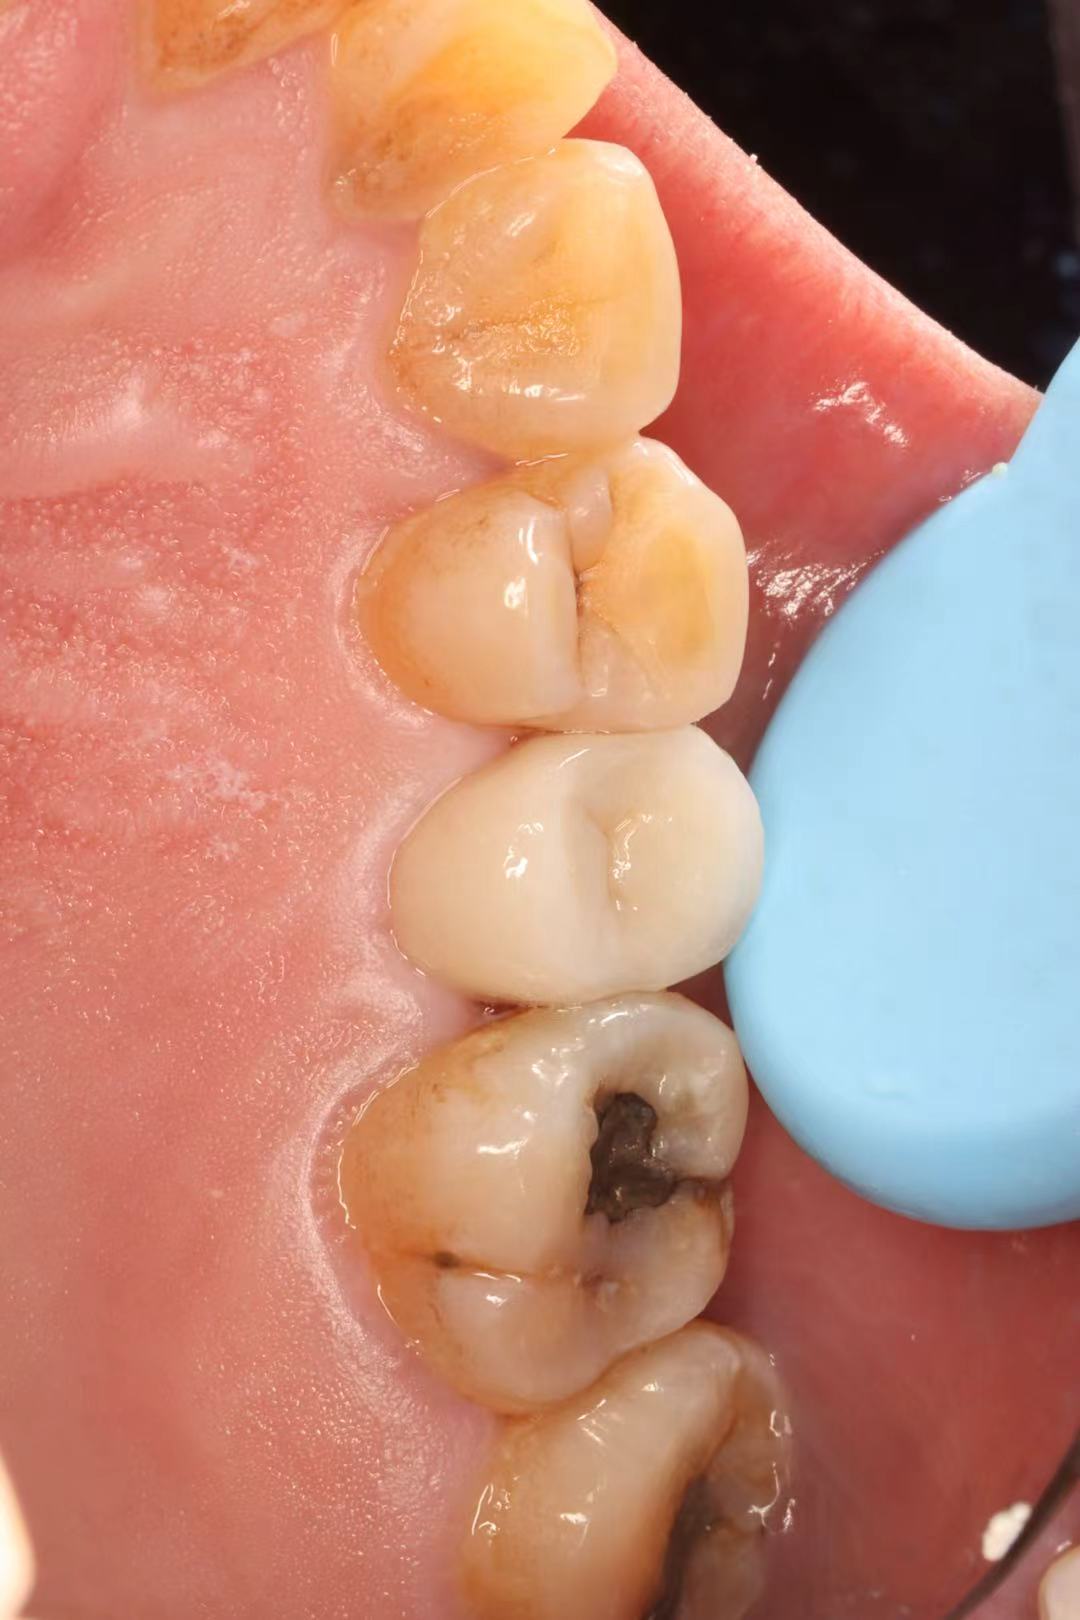

June 20, 2025: The patient's chief complaint is that endodontic treatment was performed on the right maxillary posterior tooth abroad, and a deep carious lesion has been recently detected, requiring restoration. The following are the intraoral photographs taken upon the patient's first visit: a large carious lesion is visible on the occlusal surface of tooth 15 (FDI numbering), with only the buccal wall remaining. Percussion test and cold-hot stimulation test showed no response, and yellow obturation material is visible at the root canal orifices.